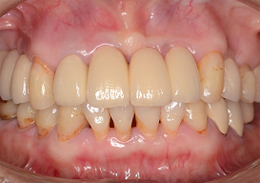

インプラントブリッジのジルコニアオールセラミックにて前歯部・審美領域の治療

- 上顎前歯2本のインプラントと右上の天然歯を、同時に色調を合わせて修復を行なった